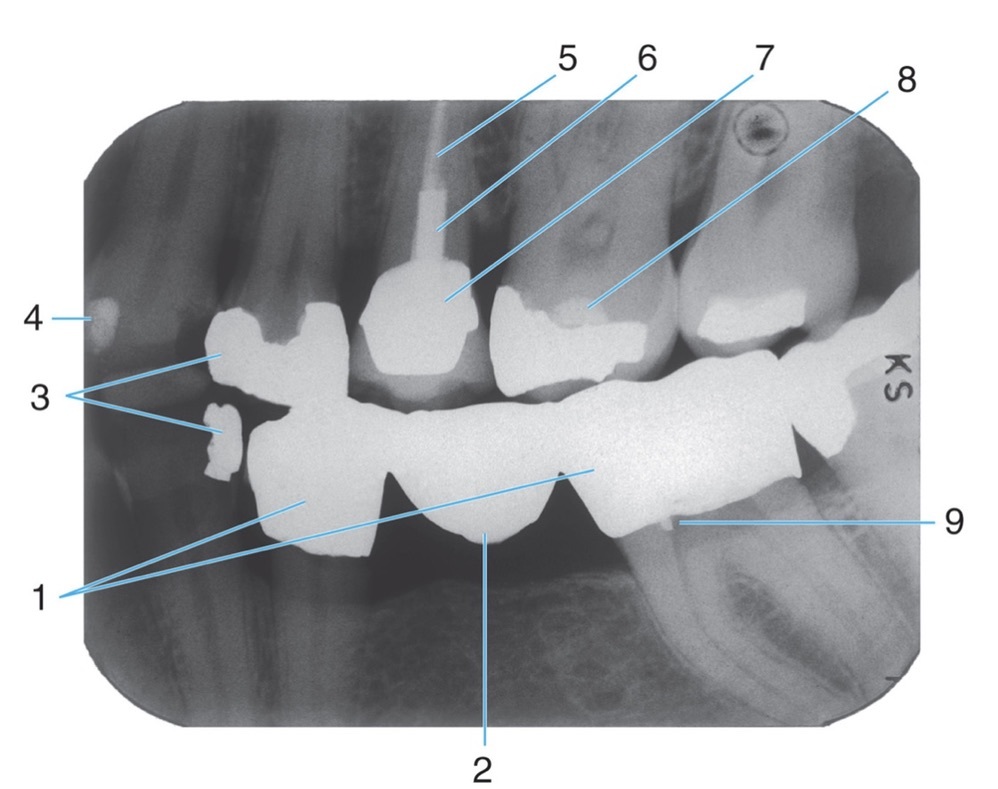

Amalgam

Radiopaque amalgam restorations

Full metal crowns form bridge abutments

Name the classification of dental caries illustrated by 3

C-3 Advanced Caries

Advanced: Lesion that extends to or through the DEJ but does not extend more than half the distance to the pulp

Identify #1.

Border of maxillary sinus

Identify #5.

Lateral pterygoid

Identify #3.

Nutrient foramen

6.

Post and core